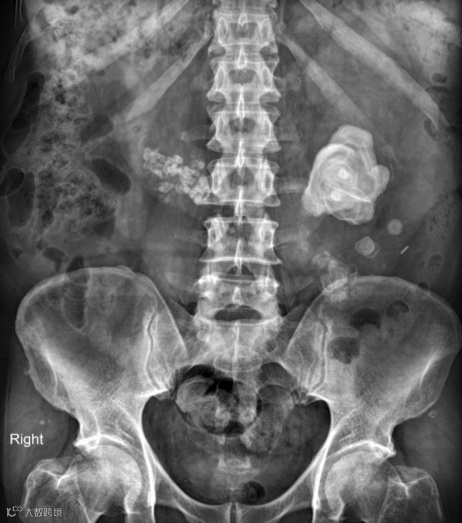

男,55岁,马蹄肾合并双肾多发结石,右肾积水(泌尿系气泡为导尿术后改变)。